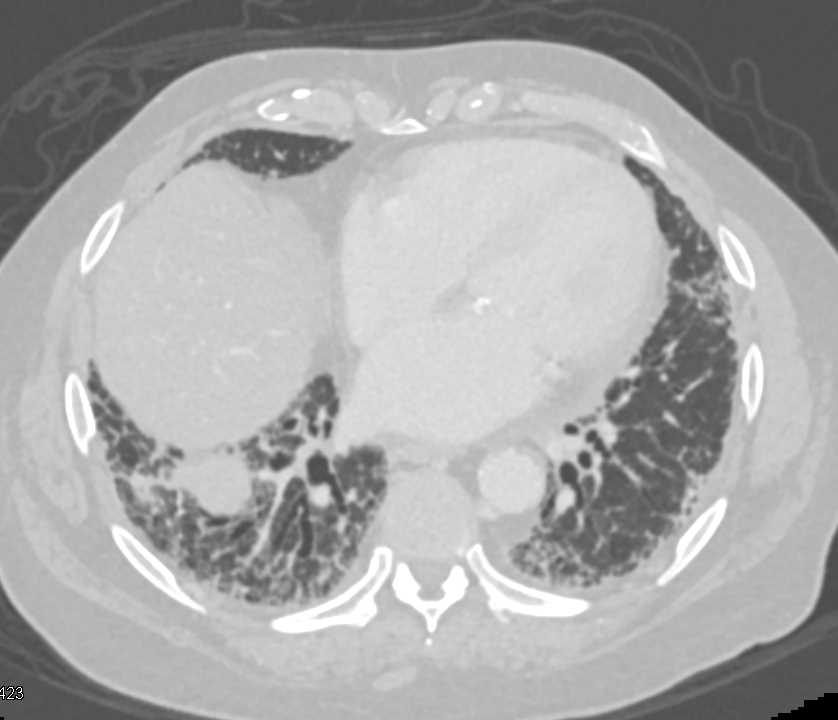

Aspiration Pneumonia in Patient with Congenital Heart Disease